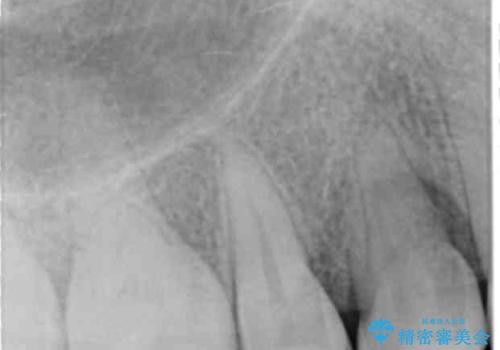

レントゲンで、右上4番の近心の垂直的骨欠損があり、抜歯を行うこととしました。

垂直的骨欠損は咬み合わせから起こったものと推察されました。

右上4の垂直性骨欠損については再生療法を行う選択肢もありました。

しかし、過蓋咬合であり、咬頭対咬頭の咬合では根本的な解決は見込めないことから、矯正治療を希望されていたこともあり、相談の上抜歯しました。

すぐに欠損するわけではないですが、最初の噛み合わせのまま4番が欠損をしたことを考えると、ブリッジやインプラントでも咬合により負担は大きくなってしまうことが考えられます。